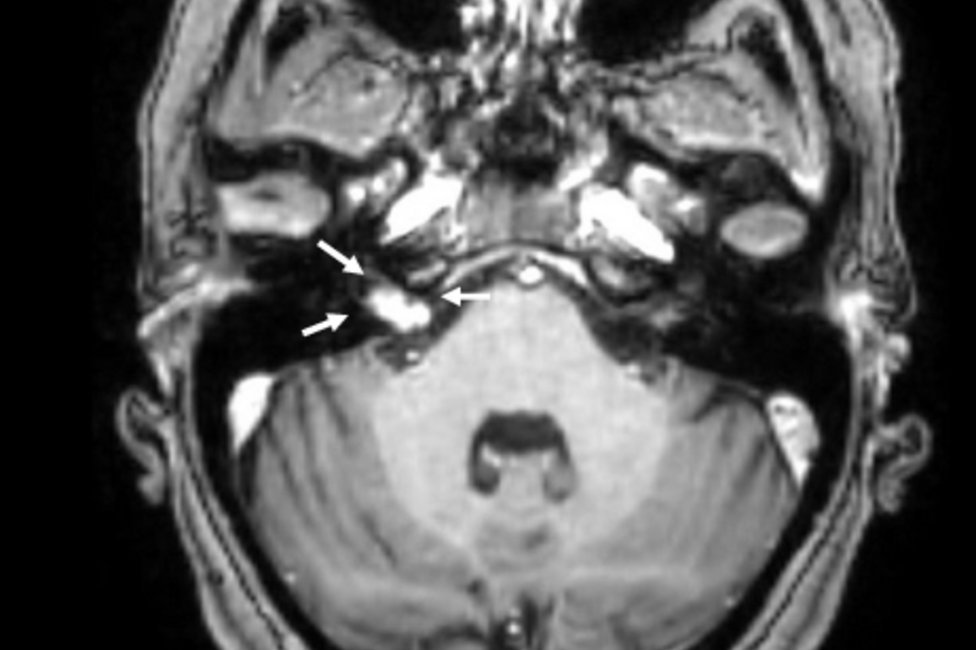

At the Department for Otorhinolaryngology 400 to 500 patients are diagnosed and (surgically) treated each week - amounting to tens of thousands of patients with various clinical pictures each year.